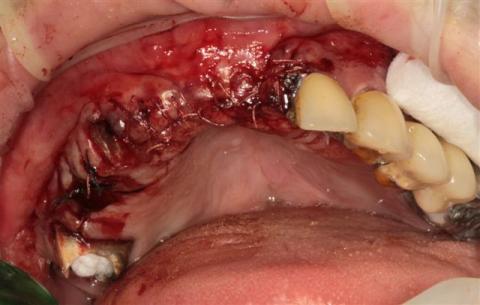

ثم جذبها حتى سقطت على الأرض ونزع اسنانها الأمامية وهي تصرخ ثم حملها إلى السيارة وقضى معها ليلته وقال لها أثناء الطريق إذا صدر عنك أي صوت سأنزع بقية أسنانك.

صعقنا من هول المفاجأة وتلمسنا أسنانا قبل أن نطلب منها أن ترينا فمها .